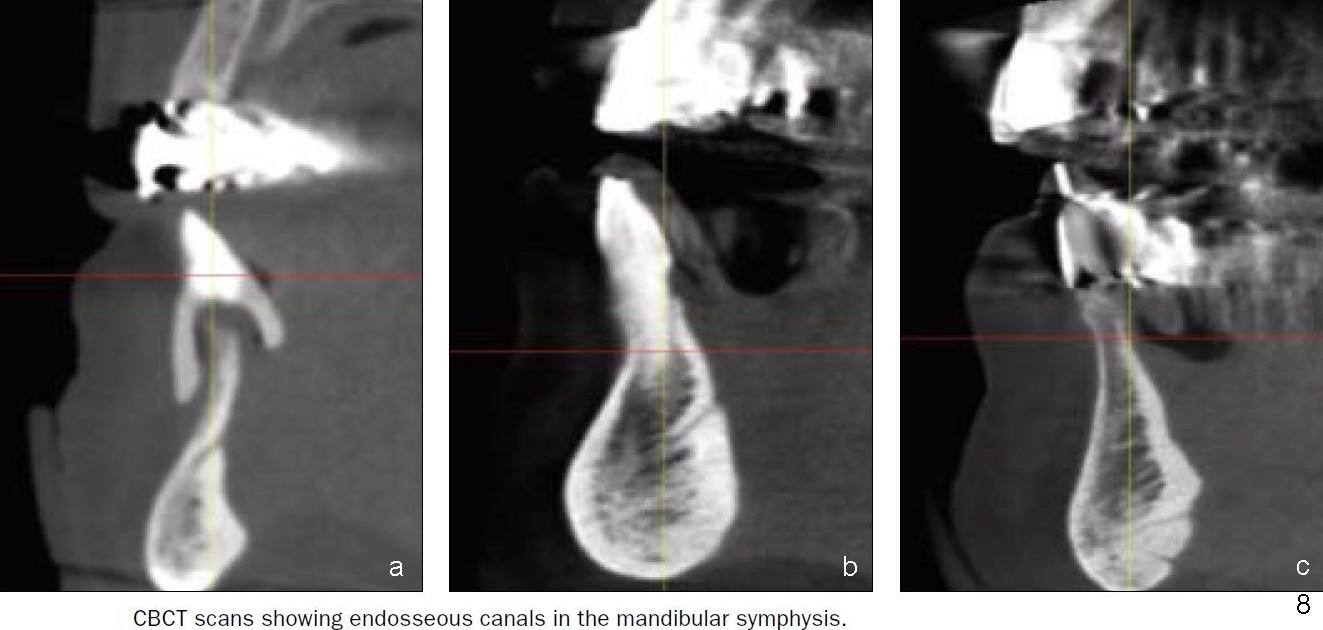

舌动脉(Lingual artery)是颈外动脉(External carotid artery)第二个前分支(图一),舌动脉末分支是舌下动脉(Sublingual artery)。舌动脉行于下颌骨舌侧(图二),它末分支舌下动脉中止于下颌骨切牙舌侧(图三),舌下动脉与颏下动脉(Submental artery,面动脉(Facial artery)分支)有吻合(箭头)。下颌骨舌侧有多个小孔(图四):正中(a, d),侧(c, e)舌孔,主要动脉穿入(1)。全景片(图五),前牙根尖片(图六)可显示舌孔(箭头, Lingual foramen)。舌孔延伸下颌骨舌侧一半(图七),下前牙植牙造成严重出血(图十,十一,2),往往是因为舌侧骨板穿孔,研究表明牙槽骨萎缩是血管意外(舌侧骨板容易破裂)主要因素(3,图八a,图九),预防方法:术前下颌骨舌侧触诊,对危险性大的病例做CT检查;术中钻洞时做下颌骨舌侧触诊,对危险性大的病例,翻瓣,暴露舌侧骨板,保护舌侧结构,使用短种植体。